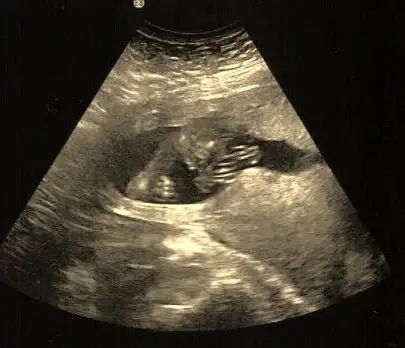

Aha buda güya cinsiyetini gösteren bir resimmis :-))))

canim eyer sen okumus olsaydin o resme bakinca bebegin ne oldugunu anlardir,hatta o resimdeki kucucuk bobreklerini bile gorurdun...

BEN tip okumadim fakat resme bakincada bisey anlamiyorum buda gayet normal ;siz gördügünüz cinsiyeti söylerseniz sevinirim :-)